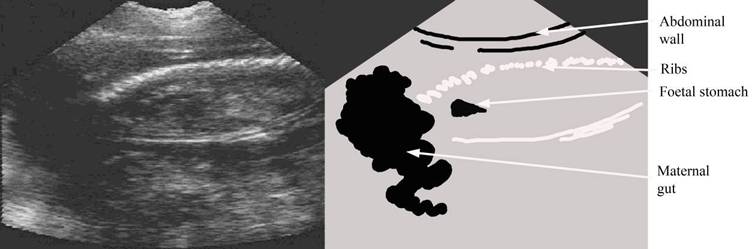

80+ days Bone in foetus becomes more obvious, but foetus can be difficult to see against the general mother background.  Note maternal gut can look like uterine vesicle but there is no distinct edge.  It can become difficult to see the foetus against the maternal abdomen as the allantoic fluid reduces in prominence

repro draw 86 day pic label.jpg